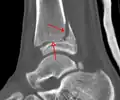

A triplane fracture of the ankle as seen on CT A triplane fracture of the ankle as seen on CT

CT

CT scans may be indicated when there is concern for a highly comminuted fracture or a fracture involving the joint surface.[10] This imaging may be used for surgical planning.

- Triplane fractures are a special type of fracture that involves the immature skeleton. It has a coronal plane in the metaphysis, an axial plane in the physis, and a sagittal plane in the epiphysis.[15]